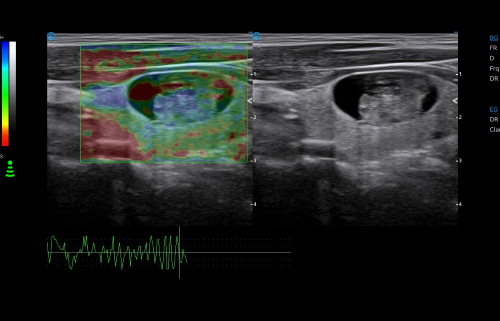

- Category: Color Doppler

· CHI visualizes blood perfusion status in real-time with high image contrast to detect micro lesions and outline tumor.

· HRI QA assesses hepatic steatosis by quantitative results with multiple sampling points available.

· Strain Elastography assists in analyzing tissue stiffness to detect potential abnormalities.